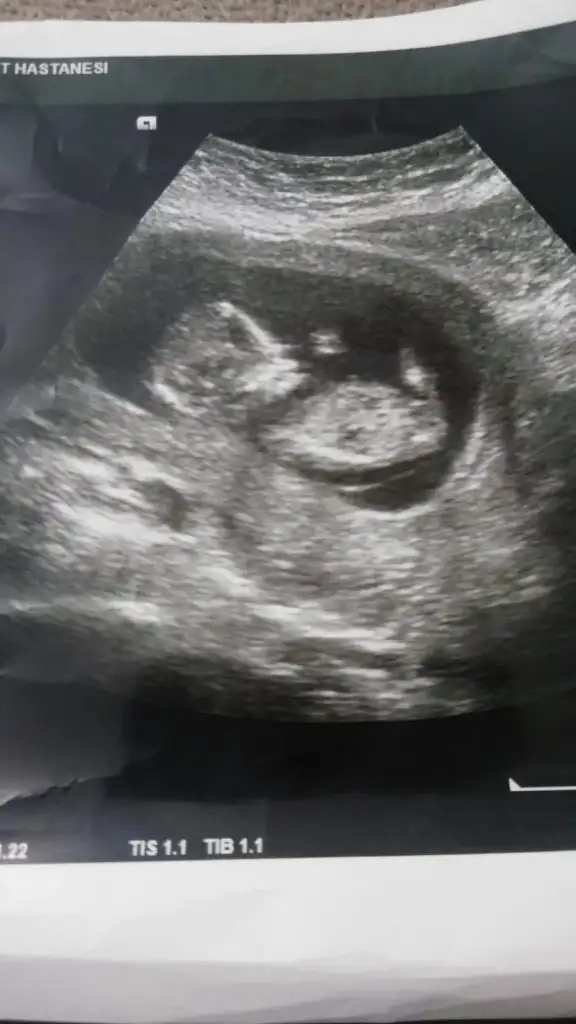

Bizede bakabilirmisiniz acaba 18.haftaya girdik daha cinsiyetimizi öğrenemedik yardımcı olursanız seviniriz 😊

Nubu erkek gibi canım kaç haftalıkta benzetti hayırlısı olsun sizin için başka usg varmı zorladım çünki usg tam net degil yakınlaştırınca puslanıyor usg minik çünki 😊

Ayda bir gidiyorum diğer ultrason görüntüsü 8 haftalık ordan anlaşılmaz diye düşünüyorum.işte 12.haftada cumartesi günü gittigimde doktor pek emin değilim bacak arasını pek göremedim değişebilir ama kız gibi dedi.telefonumun arka kamerası bozuk onle çekiyorum o da çok net çekmiyor size daha yakın bi foto atayım net değilse sonra eşimin teliyle çekerim çünkü başka ultrason görüntüsü yok maalesef. Belki kafa yapısı ile ilgili de bi tahmininiz olur .